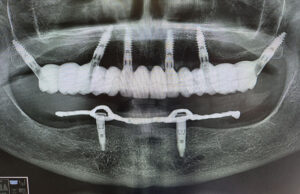

Quali sono i passaggi per arrivare ad ottenere una tale precisione? Tutto inizia dalla prima visita, dove attraverso un’ esame clinico e radiografico, si cercherà di capire se il paziente è idoneo ad una chirurgia implantare. Successivamnete inizierà la seconda fase, la più delicata, dove saranno rilevate le impronte digitali, verrà eseguita una tac volumetrica, e successivamente verranno scattate le fotografie intra ed extraorali. Nel caso del paz edentulo verrà ribasata la sua attuale protesi e scansionata, in maniera tale da poter creare una dima chirurgica perfetta per la tac

Successivamente inizierà la fase di progettazione, dove un programma dedicato elaborerà tutti i dati acquisiti. Inoltre verra’ coinvolto il Tecnico, che svilupperà il progetto Protesico definitivo, da sottoporre ad approvazione del paziente prima dell’intervento

Dopo aver stabilito la nuova estetica del paziente, verranno progettati gli impianti e successivamente la dima chirurgica.